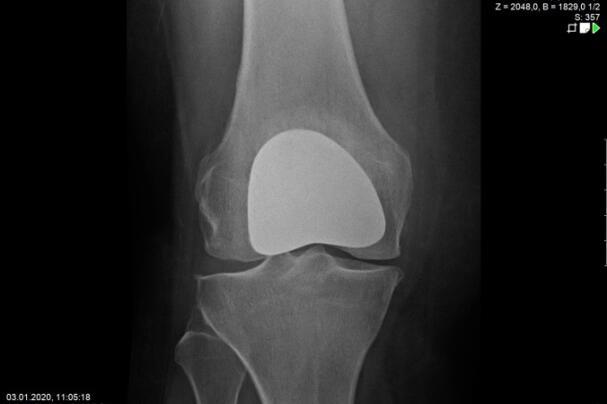

Endoprosthetics of the knee joint is an effective procedure for the treatment of symptomatic advanced wear and tear of the knee joint (gonarthrosis). If the X-ray shows a complete loss of joint space width under load, the complaints persist for more than 6 months, and the conservative therapy options have been exhausted, there is probably an indication for treatment with an artificial joint replacement (endoprosthesis). It must then be clarified which type of prosthesis is required, because today we have a large number of implants available. We distinguish between partial joints and full prostheses, and in the case of full prostheses we again distinguish between the degree of coupling of the prosthesis. If only parts of the joint are affected, only these have to be replaced and partial joints can be used. The so-called sled prostheses on the inner and outer side of the knee joint, as well as the sliding bearing replacement for problems on the kneecap, have both proven themselves effective. With full prostheses, we again differentiate between the degree of coupling of the prosthesis. Anterior and posterior cruciate ligament-supporting prostheses (surface replacement) partially coupled implants that support the inner and outer ligaments and coupled implants for complete loss of knee ligament and capsular function are used. Partially and fully coupled prostheses usually have to be inserted with stem components.